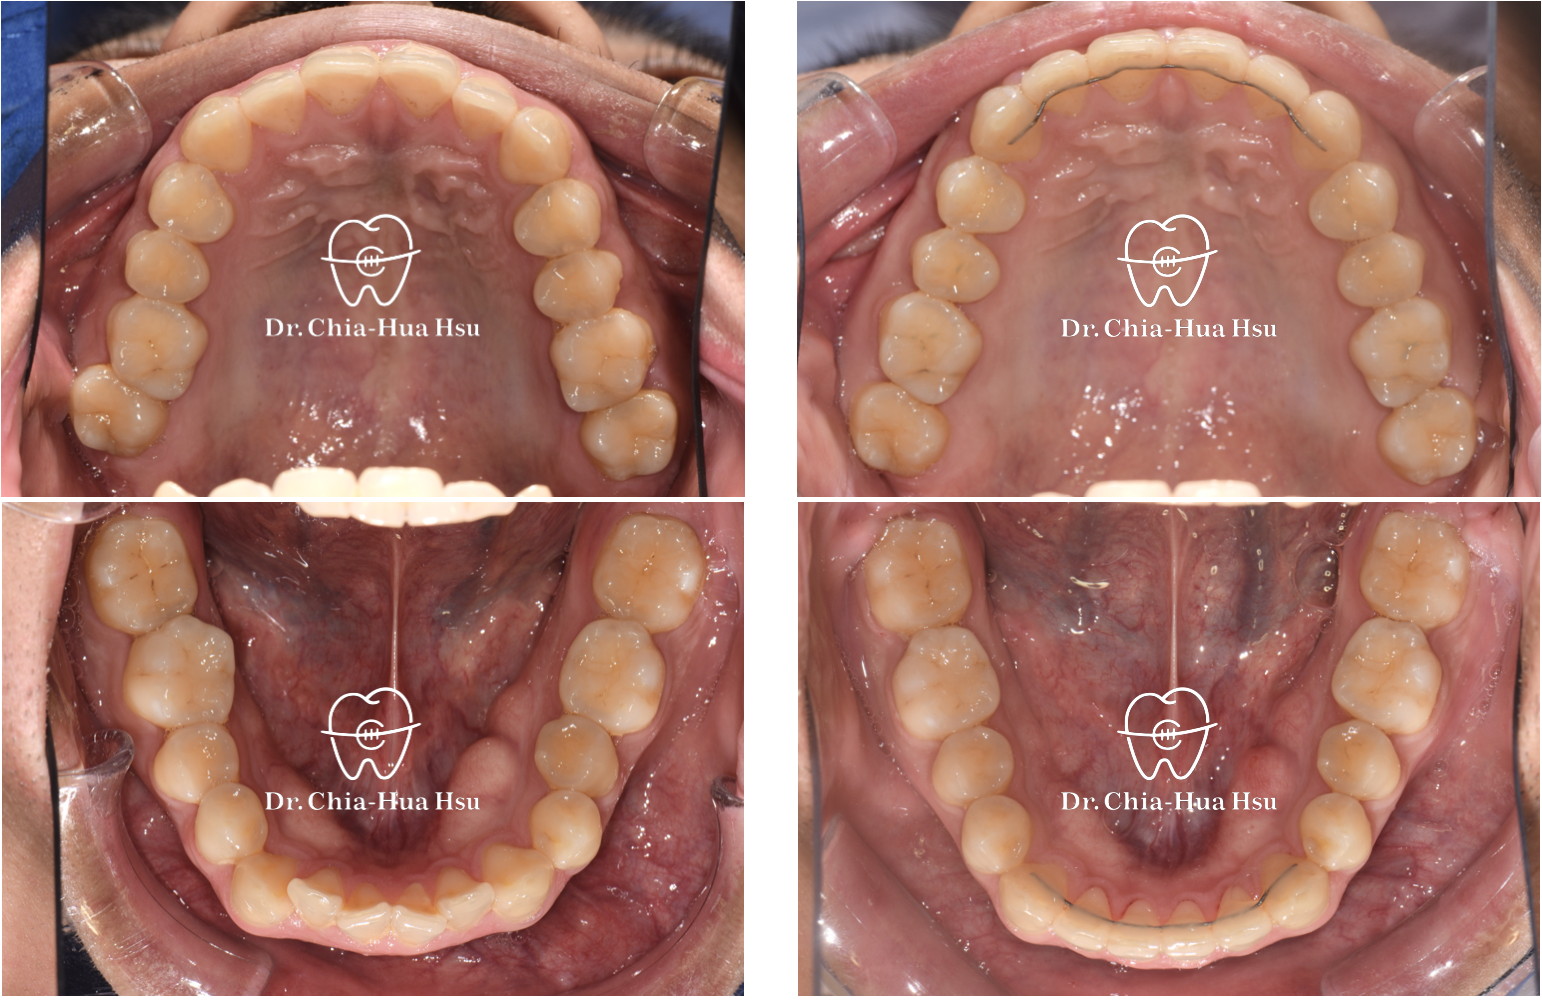

治療前

治療後

治療前

治療後